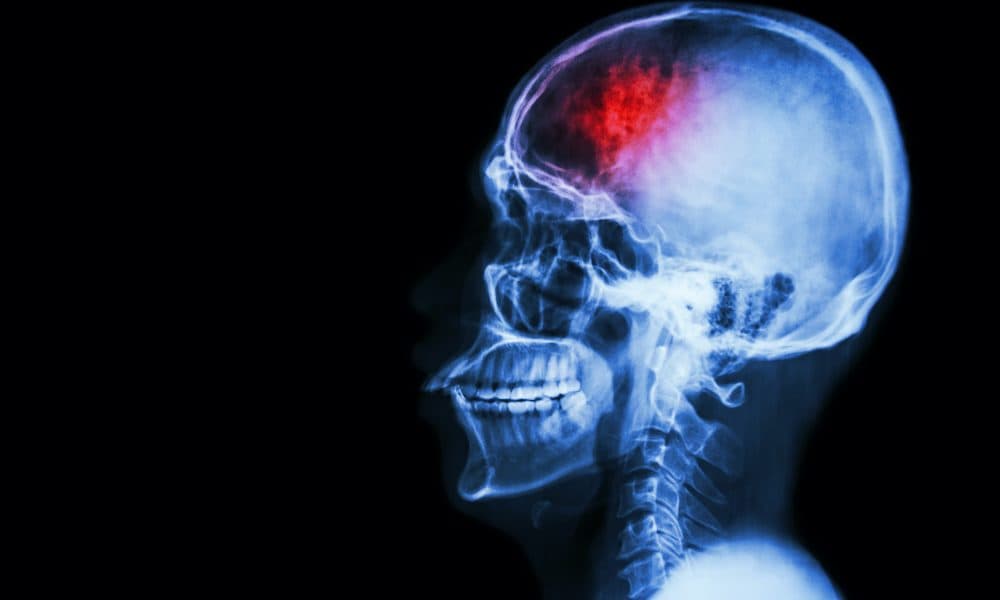

Israeli stroke rehab tech startup BrainQ has raised US$40m (£29m) in funds to support hospital trials among stroke survivors.

Its new funding will be used to support a multi-centre trial of the stroke rehab tech among ischemic stroke survivors in selected US hospitals.